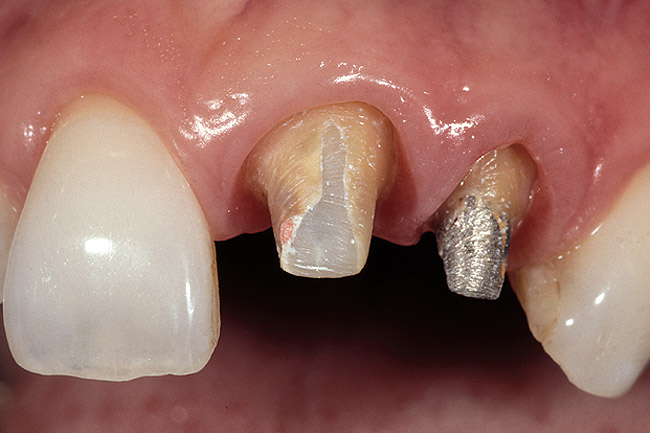

Figure 13  A patient who will require the removal of the left lateral incisor because of a split root. Due to the poor condition of the existing teeth, a bridge will be placed from the right central to the left cuspid. The patient declined an implant and is concerned about future recession.

Figure 13

Figure 14  Very dark roots and 3 mm of sulcus depth make the possibility of recession a concern. On the incisors, the decision was made to perform a gingivectomy and create a 1-mm sulcus, followed by placing the margins 0.5 mm below tissue. On the canine a gingivectomy would result in an excessively long tooth compared to the opposite canine, so the decision was made to prepare one-half the depth of the 3-mm sulcus below tissue and hope for no recession. If any occurs, the margin should remain below tissue.

Figure 14

Figure 15  The gingivectomy on the incisors was performed, leaving a 1-mm sulcus depth.

Figure 15

Figure 16  The first step in controlling margin placement is to prepare the tooth even with the gingival margin.

Figure 16